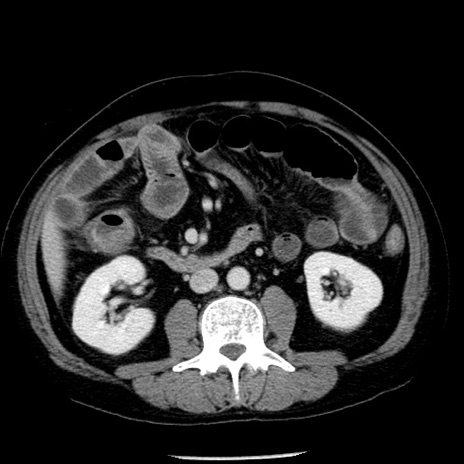

冠状断像

【症例】40歳代男性

【現病歴】2日前から胃痛あり。徐々に周期的な激痛に変化した。本日になっても激痛があるため受診。

【身体所見】意識清明、BT 38-39℃台あり、腹部:膨満、やや硬、右下腹部に圧痛あり。

【データ】WBC 8500、CRP 23.26